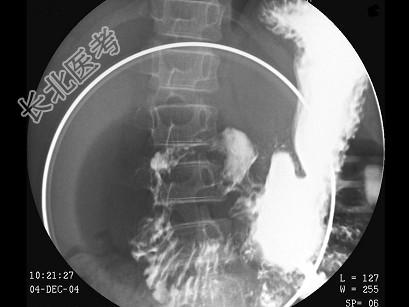

- 多项选择题男,12岁, 上腹痛1周,无规律, 无黑便史。体检:剑突下有压痛, 结合图像,最可能的诊断是 ( )

D、十二指肠溃疡